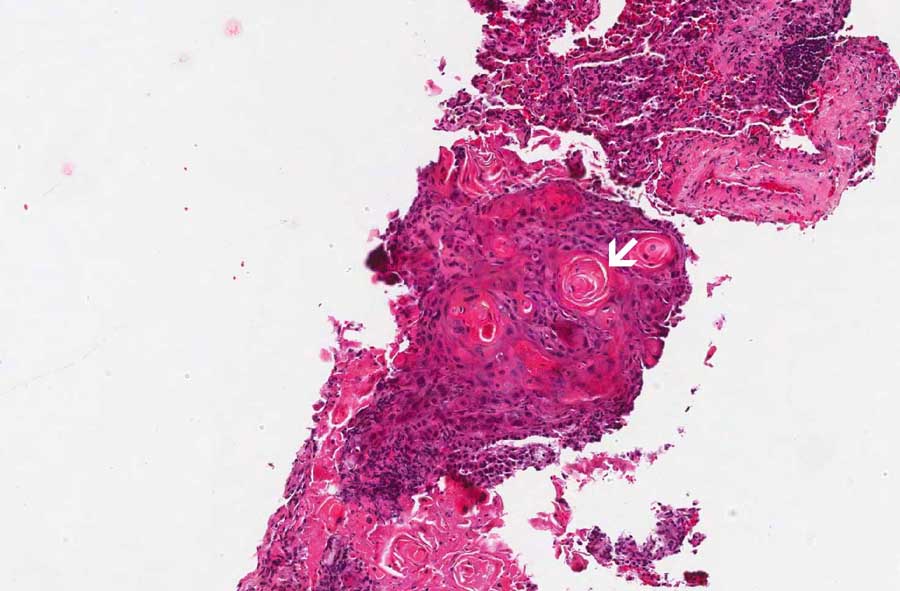

1: Note the keratinizing pearls (arrow in the low-magnification

image) and the intecellular bridges (arrow in the high-magnification

image. |

The salient features are the keratin pearls (area 1) which is a

diagnostic feature of squamous cell carcinoma. Intercellular bridges

are also present which is also a classic feature of squmous cell

carcinoma.